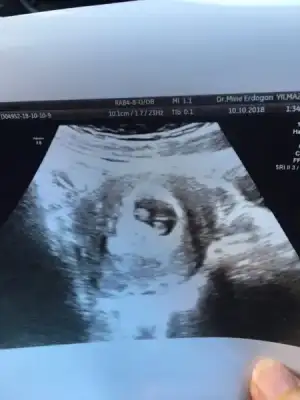

Kızlaaaar :emir_bebek:Kalp atışını dinletti ama 5 sn falan bi daha dinletirmisiniz dedim kaydetcektim bebeğe zararı olur bitanem bi daha ki gelişinizde dinleyelim dedi :) 3 hafta sonra gitcem bida.

Eklentiler

• E84D4191-3706-48DC-9DD7-6D065AABAB4C.webp

E84D4191-3706-48DC-9DD7-6D065AABAB4C.webp

12 KB · Görüntüleme: 162